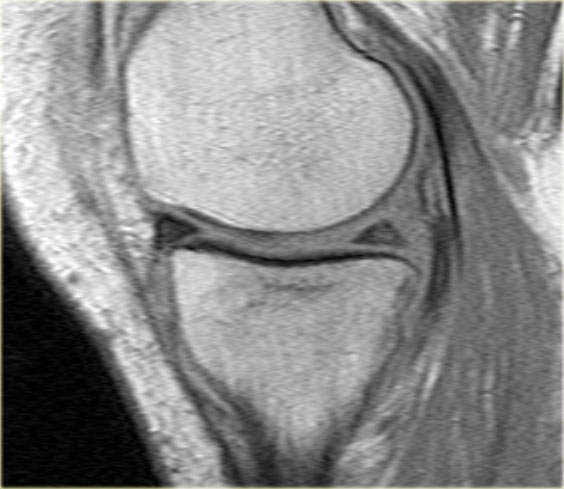

Hãy quan sát hình ảnh bên trái và cố gắng xác định vấn đề của sụn chêm này là gì.

Sau đó tiếp tục xem các hình ảnh liên tiếp tiếp theo của cùng bệnh nhân này.

Như bạn đã đoán được qua tiêu đề của đoạn này, đây là một trường hợp sụn chêm lật (flipped meniscus).

Sụn chêm lật là một dạng đặc biệt của rách dạng quai xô (bucket-handle tear).

Sụn chêm lật xảy ra khi mảnh vỡ của sừng sau bị lật ra phía trước, khiến sừng trước của sụn chêm có vẻ to hơn bình thường.

- Sừng sau quá nhỏ và sừng trước có vẻ to hơn với đường viền không đều.

- Thoạt nhìn có vẻ như có một đường rách dọc ở sừng trước, nhưng thực chất phần sau của cấu trúc này chính là phần lật của sừng sau bị rách.

Cấu trúc phía trước là sừng trước.

Cũng cần lưu ý tình trạng phù tủy xương khu trú và dấu ấn lõm sụn khớp. - Cấu trúc phía trước là sừng trước.